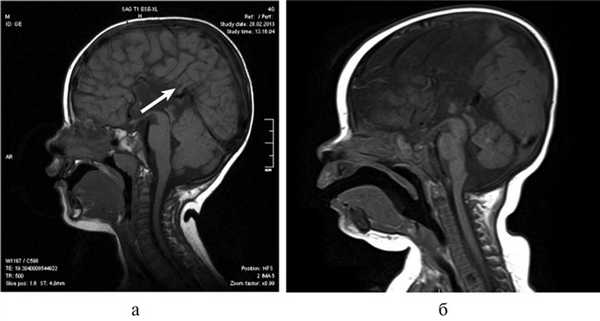

Важной находкой при АМТ на МРТ является параллельная ориентация тел боковых желудочков по отношению друг к другу (рис. 4, а), расширенные фронтальные отделы желудочков, так называемый «симптом ухвата».

Рис. 4. МРТ головного мозга больной К., 4 года. АМТ. Аксиальная проекция: а — аномальная параллельная ориентация тел боковых желудочков по отношению друг к другу (стрелка); б — фронтальное сечение: деформация передних и задних рогов боковых желудочков, своеобразный U-образный характер фронтальных отделов боковых желудочков (стрелка).

При МРТ мы обращали внимание также на описанное в литературе [12] изолированное расширение задних рогов — кольпоцефалию, обусловленную гипоплазией ассоциативных трактов белого вещества затылочных долей. Диагностический ряд на МРТ дополняют отсутствие нормально сформированных перикаллезных извилин (рис. 5, а) и радиальная центростремительная позиция борозд медиальной поверхности теменной доли (рис. 5, б).

Рис. 5. МРТ головного мозга больного А., 3 года. АМТ. а — сагиттальная проекция. Отсутствие нормально сформированных перикаллезных извилин (стрелка), б — высокое положение III желудочка, радиальная центростремительная направленность борозд медиальной поверхности теменных долей.